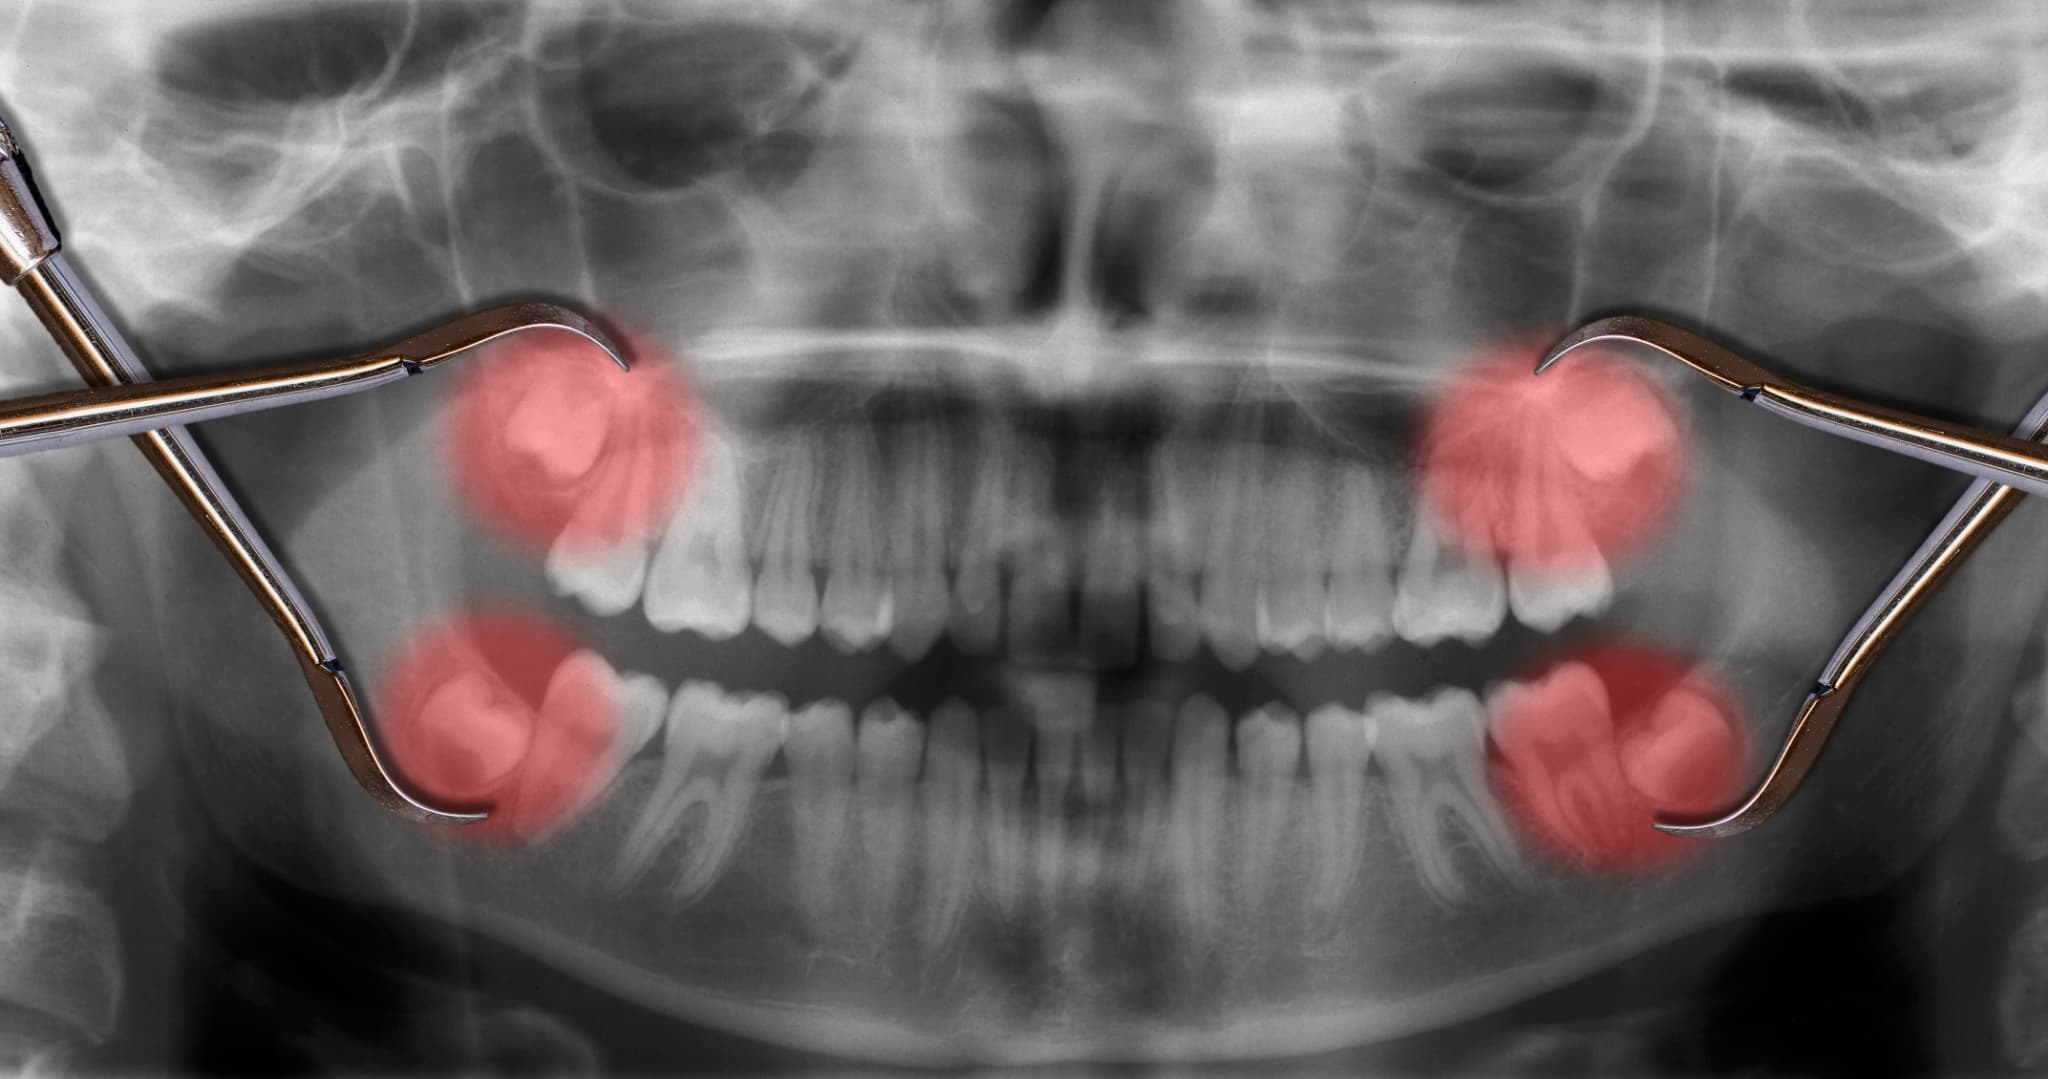

口内の状態確認

まずはレントゲン検査を行い、親知らずの生え方や斜めに生えている角度、周囲の歯への影響などを詳しく確認します。また、虫歯や歯周病の有無、歯茎の炎症の程度なども把握します。これによって、抜歯の必要性と抜歯方法、抜歯のスケジュールを判断します。

検査

まずは、親知らずが斜めに生えている理由や今後の見通しを含めた、詳細な検査を行います。CT検査やレントゲン検査などで親知らずの位置や向き、隣接する歯との位置関係などを詳しく調べます。